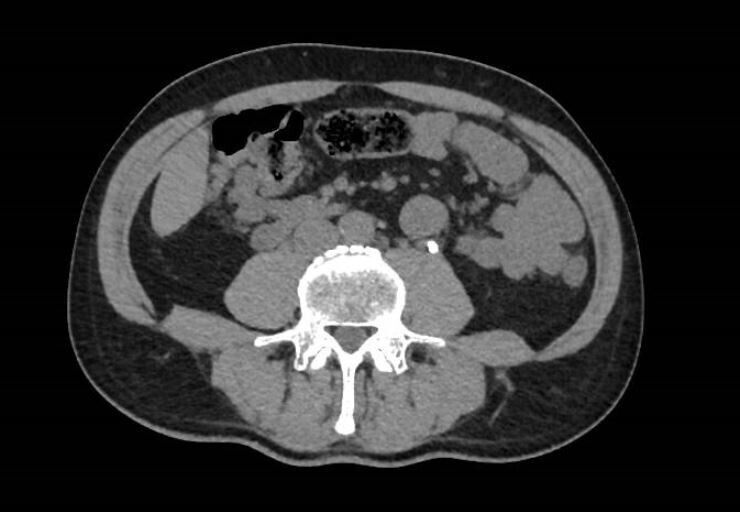

Voici les images clés du scanner réalisé (figures 1 et 2) : Figure 1 (Source : Théo Arber, La Revue du Praticien)

Figure 2 (Source : Théo Arber, La Revue du Praticien) Il n'y a pas d'abcès rénal.